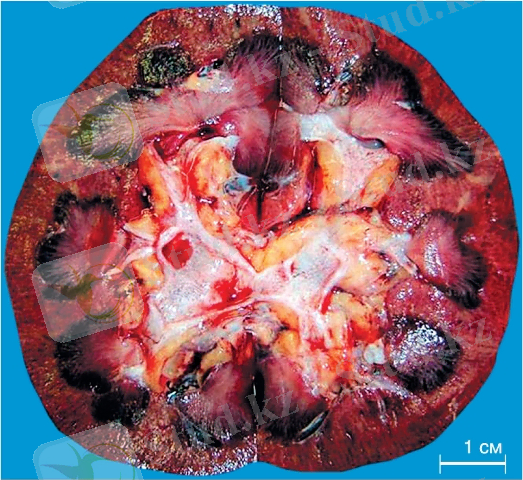

3. Макропрепараттар (a, б) . Бүйректің цианозды индурациясы: бүйрек мөлшері бойынша ұлғайған, тығыз консистенциясы (индурациясы), тегіс беткейімен, кесіндісінде, қыртысы мен медулла кең, біркелкі толық қанды, цианотикалық (цианотикалық) .